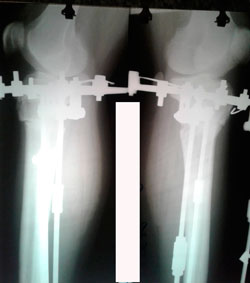

Исходник 38 лет.

Дата операции - 16.03.2020